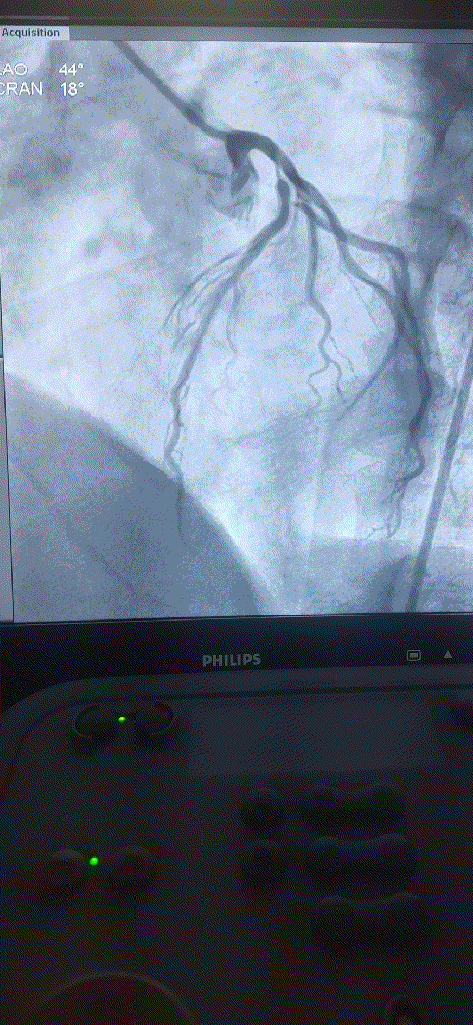

How do you explain this ? 99% occlusion still TIMI 3 flow ?

A. It could be a parallax error. Lesion may not be tight. Should be seen in other views.

B . Forcible Injection by the operator, make it an artificial TIMI -3 flow.

C .Such flows are very much possible .It Indicates a healthy distal micro-circulation a vascular bed in a fully dilated mode.

D. TIMI flow is not reliable here . We need TIMI frame count to confirm.

Follow up questions

1.How much will be the FFR ?

Likely to be less than . 8 definitely , but surprises can happpen

2.Can he be asymptomatic ?

Unlikely.

Final message

Coronary occlusions are ominpresent . While we have mastered the art of successfully taming these anatomical enemies , we are still very much ignorant what these lesions actually do, to the physiology, inspite of half a dozen flow reserve Indices we have.(FFR,iFR, rFR,qFR, dP/dT ,etc)

The question is, at what level of obstruction, it really limits the coronary bllod flow significantly ( both at rest and exertion) . One thing is clear , it is higly variable & Individualistic, the secrets of which lies deep, in the domain of invisible micro-vascular network integrity.

Counterpoint

TIMI flows may no longer be valid in non-ACS situations. The name TIMI , by itself carries flow after thrombolysis. For some unexplained (& debatable ) reasons, we are used to apply this flow grade , in every angiographic flow scenerios irrespective of underlying clinical entity.